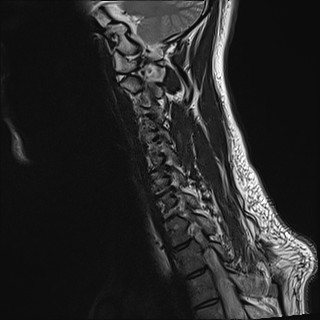

Wirbelsäule HWS

t1_tse_sag